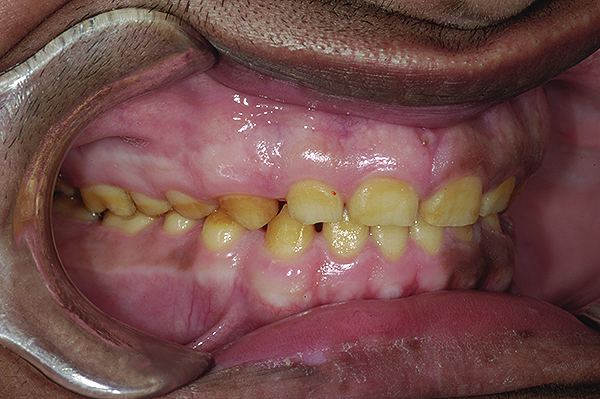

The authors report on a 21-year-old patient who presented with severe discoloration and mild sensitivity of teeth (Figure 1). The teeth visible in his smile were very short, unsightly, and unbecoming for his age.

Figure 3. Preoperative 1:2 retracted right lateral view.

Figure 3

Figure 4. Preoperative 1:2 retracted left lateral view.

Figure 4